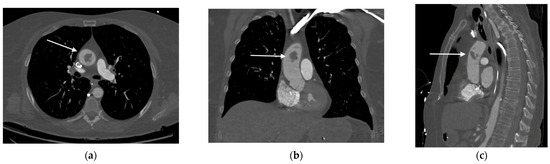

2. Case Presentation